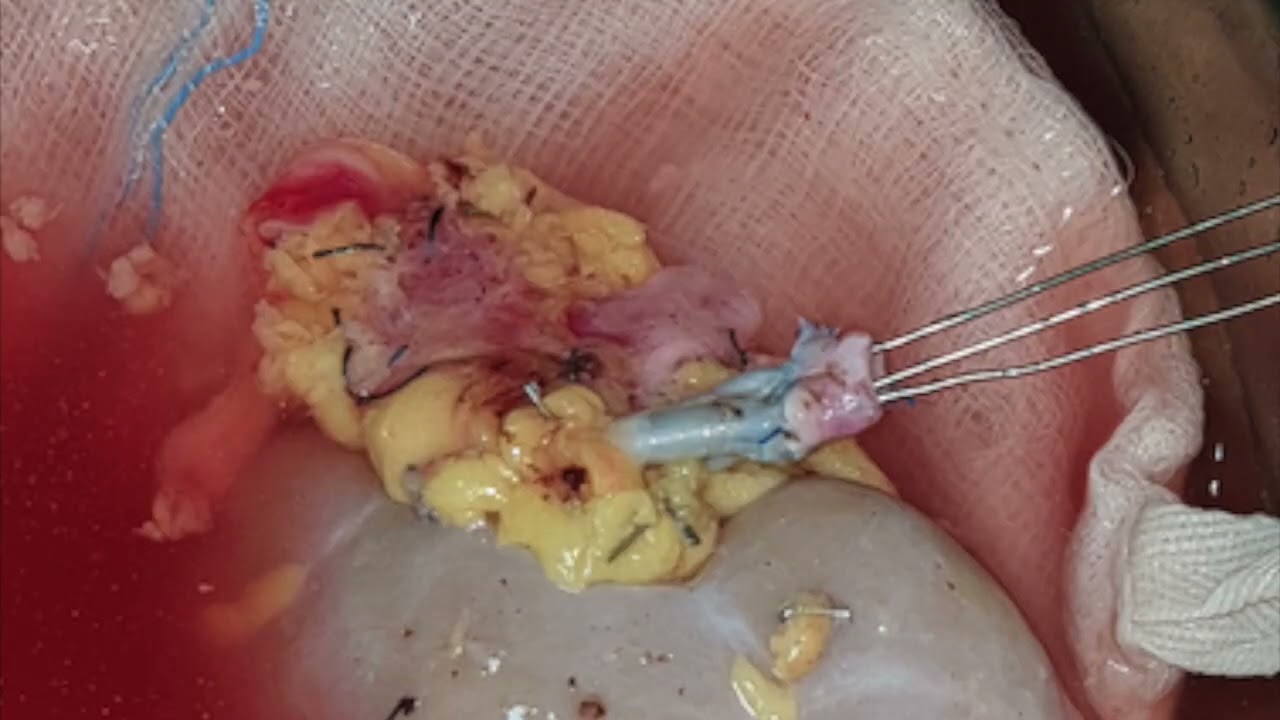

Robot-assisted radioguided surgery using a DROP-IN gamma probe